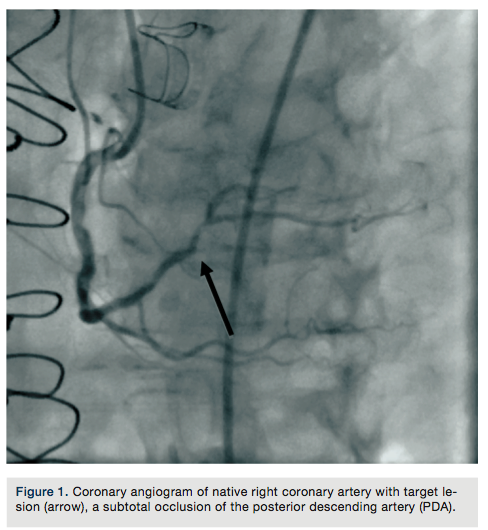

A 75-year-old female with a past medical history of coronary artery disease with previous coronary artery bypass grafting with left internal mammary artery (LIMA) to left anterior descending (LAD) artery, saphenous venous graft (SVG) to ostial medial (OM) branch, SVG to postero-lateral (PL) branch, and bioprosthetic aortic valve replacement presented with progressive dyspnea on exertion associated with substernal chest pressure. She presented with no ECG changes or elevation in cardiac biomarkers. Despite optimal medical management, she continued to endorse chest pain and thus underwent cardiac catheterization for evaluation of her coronary anatomy. Catheterization revealed a patent LIMA to LAD and SVG to OM, moderate disease in the SVG to PL graft, and a new, severe subtotal occlusion of the posterior descending artery (PDA) from the right coronary artery. We proceeded with intervention to this vessel using a 6 French (Fr) 0.75 Amplatz guide catheter. The index lesion was crossed with a Balance Middle Weight (BMW) guide wire (Abbott Vascular), with difficulty. Predilation was attempted with a 2.5 x 12 mm Apex balloon (Boston Scientific), but could not be advanced beyond the mid PDA. A GuideLiner catheter (Vascular Solutions) and a 1.25 x 10mm Sprinter Legend balloon (Medtronic) were advanced to the distal right coronary artery where they became resistant to advancement. The balloon was briefly inflated, but would still not advance. It was noted to have ruptured and despite aggressive tugging and pushing, could not be removed. The GuideLiner catheter could not be advanced further into the vessel to help free the balloon. It could also not be removed entirely, as it contained the shaft of the balloon. Eventually, with applied tension, the balloon shaft avulsed and remained in the distal RCA. Two different snares and two QuickCross catheters (Spectranetics) were advanced over the guide wire, but could not reach the site of the balloon. Given the tortuous anatomy and degree of calcification, it was determined that no other device or stent could be delivered, and thus the delivery wire was removed. Final angiography revealed TIMI-3 antegrade flow into the PDA, but with an obvious retained balloon tip and associated filling defect. Severe residual stenosis of the index lesion also remained. The patient remained hemodynamically stable throughout the procedure and asymptomatic subsequently. No ECG changes were identified and no regional wall motion abnormalities were seen on